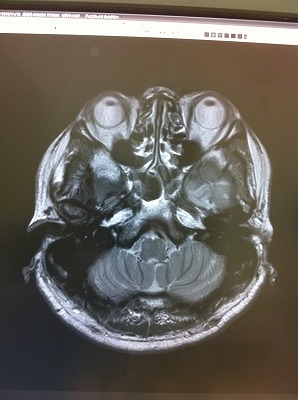

頭のてっぺんから、喉元辺りまで撮影したということで何枚か写真を見た中で、もっともグロテスク?面白い写真がこれですね。

ちょっと、気持ち悪いので、注意してください

ちょうど、目の高さを輪切りにしたものですから、、上に、目、鼻、、左右の空洞が耳、、その他はなんでしょうね?

凄いです。。自分であっても、グロイ。。。

脳が詰まっている部分、、、。考え方が歪んでいると形も歪になるのか??